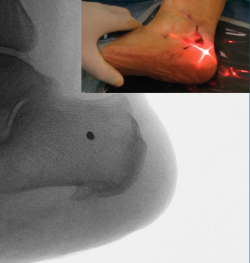

Figura 4. Imagen fluoroscópica de la fresa suelta introducida y su correspondencia en cirugía.

Ayudándose del mosquito para separar las partes blandas, se introduce una fresa Shannon 2 o 3 × 20 mm (FH Orthopedics, Mulhouse, Francia) en el vértice de la V. Comprobada la correcta posición de la fresa en la fluoroscopia (desconectando el motor de la fresa) (Figura 4), esta se avanza perpendicularmente al eje del calcáneo hasta atravesar la segunda cortical. Inclinando la fresa se pueden obtener diferentes desplazamientos, si bien, para conseguir un mayor desplazamiento, se recomienda avanzar perpendicularmente al eje. Si se quiere conseguir cierto efecto de descenso además de medialización de la tuberosidad se dirigiría la fresa en dirección de dorsolateral a plantomedial unos 15-30° respecto a la perpendicular del eje del calcáneo. Si lo que se quiere es obtener un efecto de elevación (beneficioso en el cavo posterior), la dirección sería la contraria, es decir, de lateroplantar a dorsomedial. Se podría obtener también acortamiento del calcáneo si la fresa se dirige de lateral distal a medial proximal, e incluso un alargamiento (de lateral proximal a medial distal), aunque esto último dificultaría el desplazamiento por la tensión de los tejidos(13).